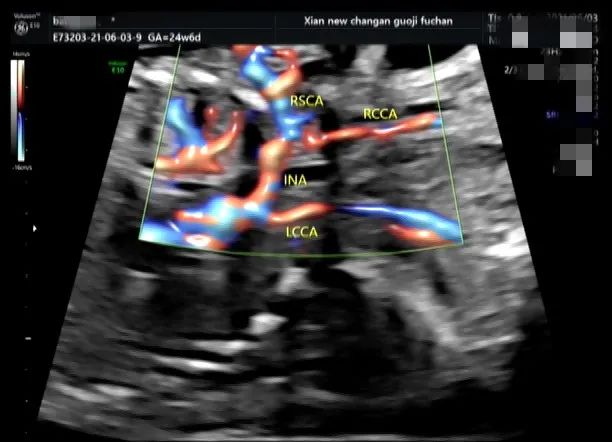

今年我科发现数例主动脉弓分支变异的病例,其中一例为较少见的单一分支,即四支血管共同起源于一支,其它几例均为两分支即左侧颈总动脉异常起源于无名动脉。

主动脉弓是由左心室发出的主动脉的延续,凸侧由右向左依次发出三大分支,即无名动脉、左颈总动脉及左锁骨下动脉。1893 年 Arthur Thomsin 首次对其进行了报道,变异率达 20% 。早期诊断其变异类型,可以为患者以后的介入手术穿刺入路、脑血管疾病及主动脉夹层的治疗提供早期的手术方案。